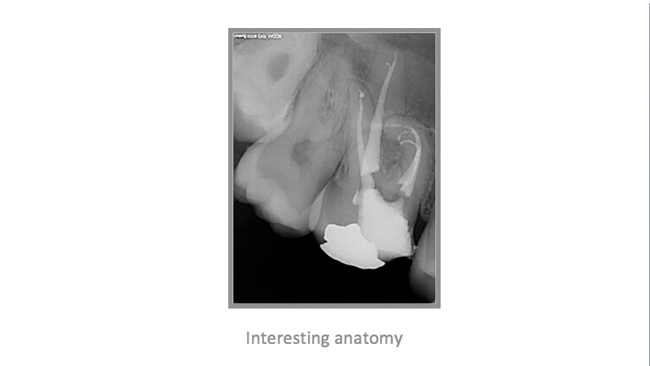

• A few Teeth Treated by Dr. Katsarsky

• A few Cases Treated by Dr. Katsarsky